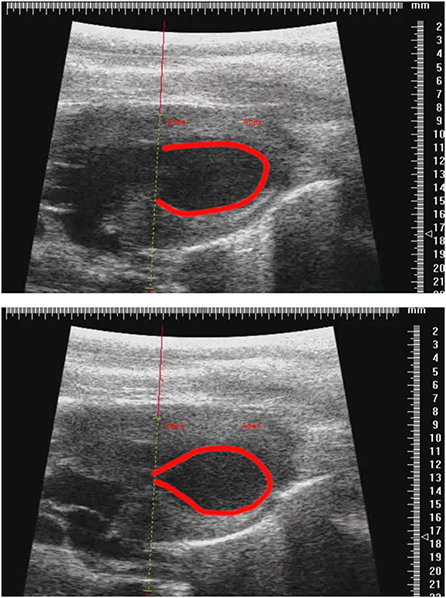

We noticed that after isoprenaline administration, animals tended to increase their body temperature, and after discussion between the two groups we determined that allowing the development of the natural transient isoproterenol-induced hyperthermia was essential for the consistent induction of TTS-like contractility in this animal model (Figure 6). Groups wishing to replicate this TTS model should pay close attention to body temperature and allow moderate hyperthermia to occur.

Figure 6. Representative parasternal long axis B-mode images of end-diastole (top) and end-systole (bottom) after induction of TTS-like contractility (base: left; apex: right), with trace (red line) drawn around endocardial border. Scale in mm.